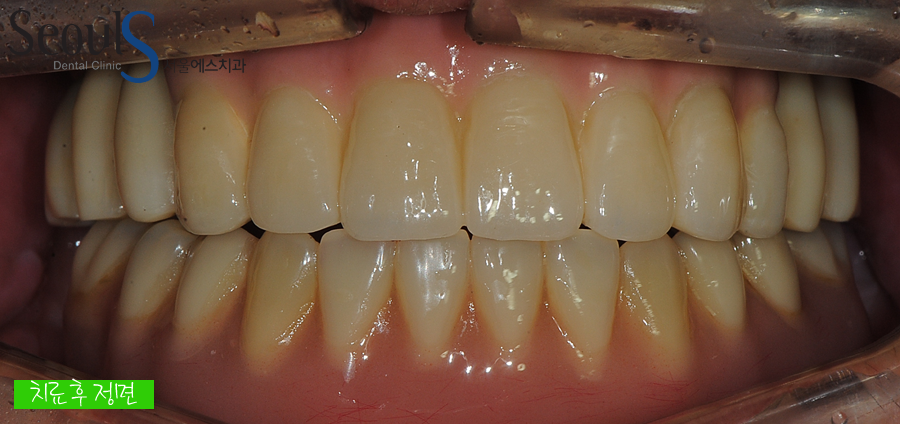

정면 치아 모습입니다

각각의 과정을 꼼꼼히 그리고 정확히 진행한 결과

정확한 임플란트 식립, 자연스러운 보철물 제작 및 결합 후 모습입니다

어떤가요? 실제 치아처럼 자연스럽게 치료가 마무리된 모습이죠^^